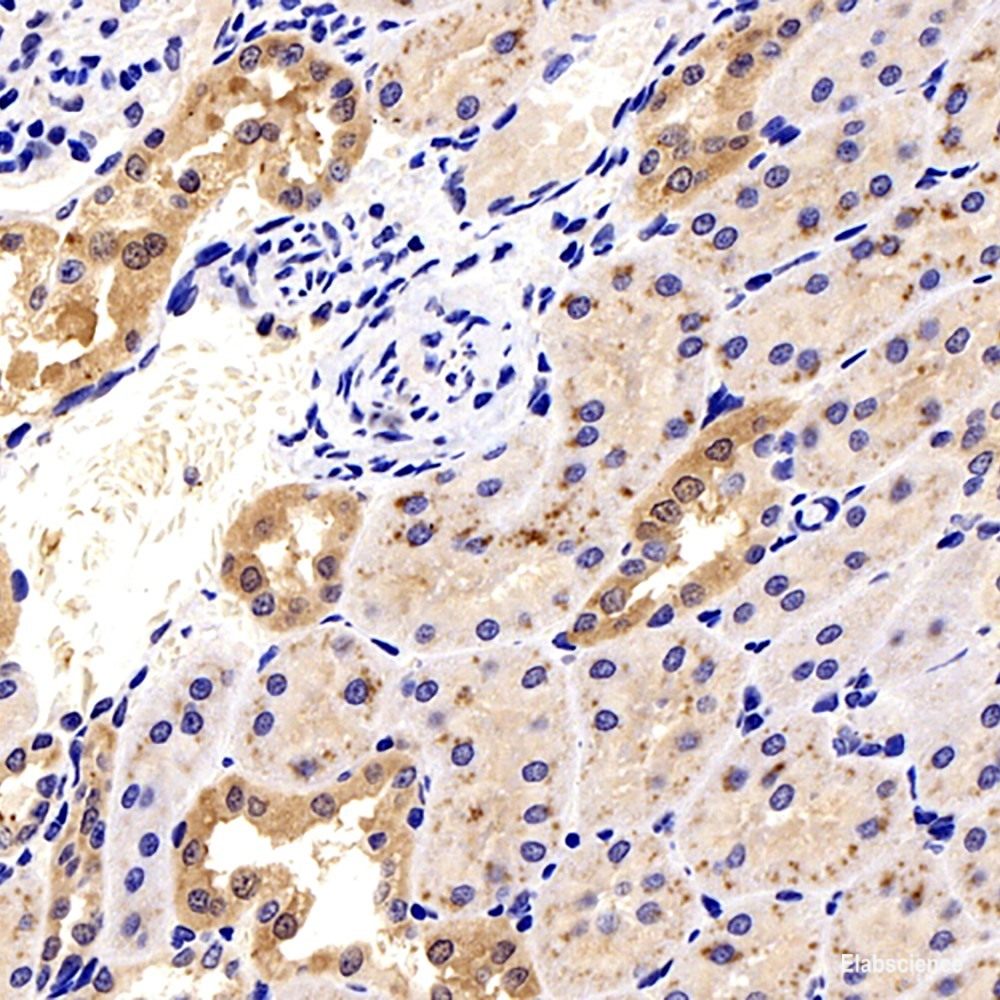

Product information "Anti-Galectin 3"

Galectins are a family of animal lectins defined by shared characteristic amino-acid sequences and affinity for ß-galactose-containing oligosac-charides . Galectin-3 contains one carbohydrate recognition domain (CRD) and a proline- and glycine-rich N-terminal domain through which is able to form oligomers. Galectin-3 is widely expressed in many normal tissues and a variety of tumors. It is found intracellularly in nucleus and cytoplasm or secreted outside of cell,being present on the cell surface or in the extracellular space . Galectin-3 is involved in various biological processes including cell growth,adhesion,differentiation,apoptosis,angiogenesis,immune response,neoplastic transformation and metastasis . Protein function: Galactose-specific lectin which binds IgE. May mediate with the alpha-3, beta-1 integrin the stimulation by CSPG4 of endothelial cells migration. Together with DMBT1, required for terminal differentiation of columnar epithelial cells during early embryogenesis. In the nucleus: acts as a pre-mRNA splicing factor. Involved in acute inflammatory responses including neutrophil activation and adhesion, chemoattraction of monocytes macrophages, opsonization of apoptotic neutrophils, and activation of mast cells. Together with TRIM16, coordinates the recognition of membrane damage with mobilization of the core autophagy regulators ATG16L1 and BECN1 in response to damaged endomembranes. [The UniProt Consortium]

| Application: | IHC |

| Immunogen: | Recombinant protein corresponding to Mouse Mac2 |